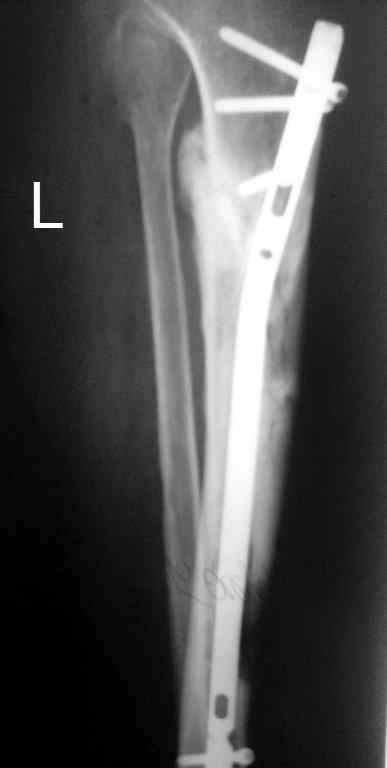

В июне 2009 года, при рассверливании канала произошел ожог передней стенки ББК. Со слов оперировавшего хирурга: «Не обратил внимания на то, что головка римера уперлась, и спохватился только в тот момент, когда прямо на глазах появилась яркая гиперемия кожи над этим местом». Никаких действий по этому поводу не предпринималось. (Интересно, а что можно было бы осуществить в таком случае?). Операция была закончена, пациент выписан. Вскоре образовался некроз, пациент лечился в стационаре. Попытка хирурга закрыть дефект ротационным кожным лоскутом не увенчалась успехом. Больной выписан.

Итак, в настоящий момент больной пришел к нам с полной нагрузкой на оперированную конечность и с такой картиной (см. приложение). Участок мягких тканей с передней стенкой нижней трети ББК, выгнил и представляет дефект 2×2,5 см. На перевязке - циркулярный(?) некроз костной трубки.

Пациенту за 70 лет. Мои соображения: 1 этап - резекция tibia + косая остеотомия fibula + «острое» укорочение + IM цемент-гвоздь с а/б + beads. 2 этап (по заживлению раны) – удаление цемент-гвоздя + (LATN) Lengthening and Then Nailing. Прошу помощи по тактике.Никита Заднепровский